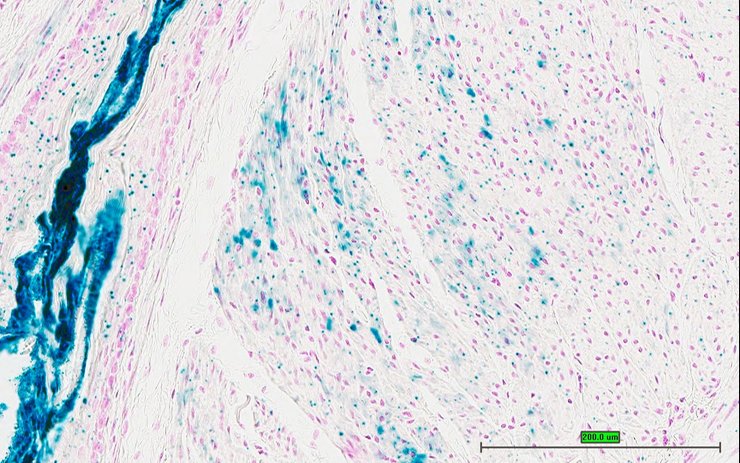

TS28: aorta Present UC Davis_1876913

Specimen UC Davis_1876914: postnatal adult; Fosbtm1b(KOMP)Wtsi/Fosb+ (more )